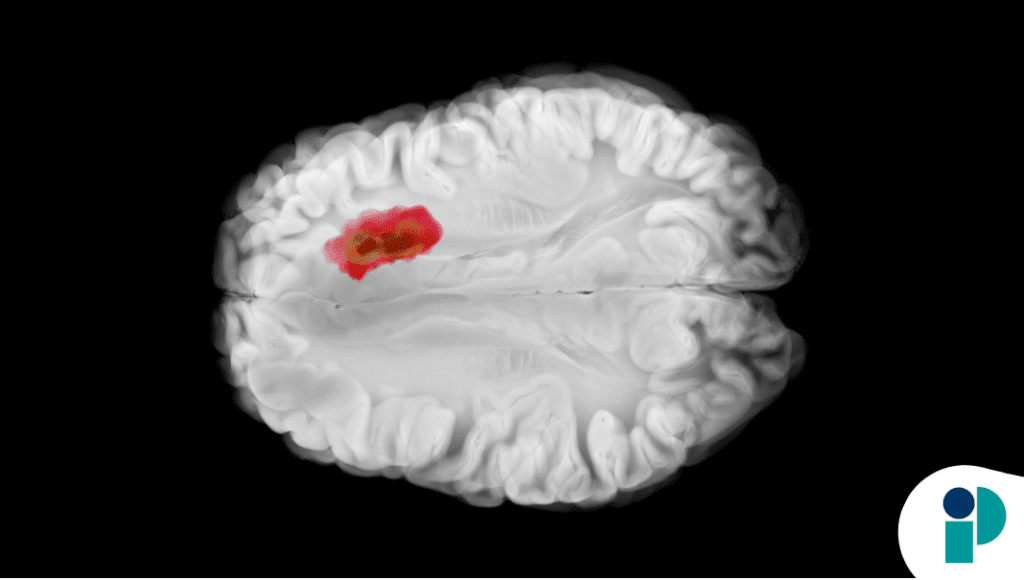

El paciente, un hombre de 23 años sin antecedentes médicos relevantes, llegó al hospital tras experimentar tres días de intensas cefaleas, pérdida de visión en el ojo derecho, náuseas y vómitos. La resonancia magnética cerebral reveló una masa extra-axial de rápido crecimiento con hemorragia intratumoral. Debido a la gravedad de su condición, se procedió a una resección quirúrgica, seguida de radioterapia con temozolomida.

“La resonancia magnética típicamente revela un tumor con realce de contraste y efecto de masa en las áreas corticales, que a menudo involucra el lóbulo parietal o temporal, con manifestaciones multifocales ocasionales, incluida la diseminación leptomeníngea. Se pueden observar necrosis, cambios quísticos, hemorragia y calcificaciones”, mencionan en la discusión del caso.